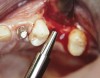

At the time of surgery, local infiltrative anesthesia was administered (lidocaine 2% with epinephrine, 1:100,000). A full-thickness mucoperiosteal flap was raised. The initial osteotomy was performed on midcrestal bone using a rose-headed bur. To prepare the osteotomy site for implant placement, sequential alternating osteotomes with variable conicity were used, drilling 2-mm shorter than the length of the implant to be placed (Figure 3A and Figure 3B). The implants presented initial primary stability (Figure 4), the cover screws were placed, and the implants were submerged for a healing period. The tissue was approximated, and the patient was instructed not to wear any denture or to place pressure on the healing site.

Figure 3A and Figure 3B Alternating osteotomes with variable conicity used to perform the alveolar remodeling in the area of tooth No. 24.

Figure 3a  Alternating osteotomes with variable conicity used to perform the alveolar remodeling in the area of tooth No. 24.

Figure 3a

Figure 3b  Alternating osteotomes with variable conicity used to perform the alveolar remodeling in the area of tooth No. 24.

Figure 3b